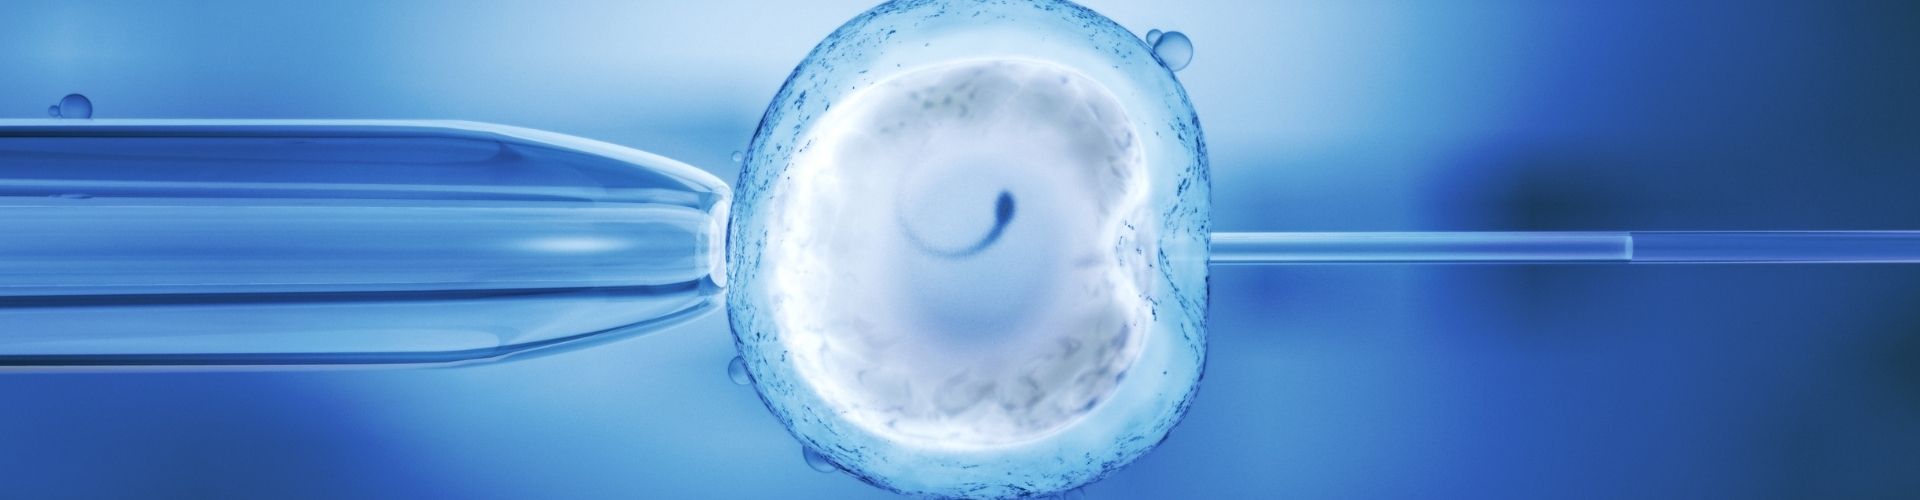

Tüp bebek ve aşılama, çocuk sahibi olmak isteyen çiftler için modern tıbbın sunduğu iki önemli seçenektir. Her ikisi de doğurganlık sorunlarıyla başa çıkmak için kullanılan yöntemler olmasına rağmen, temel çalışma prensipleri ve uygulama şekilleri açısından birbirlerinden farklılık gösterirler. Bir tüp bebek uzmanı olarak, bu iki yöntem arasındaki farkları netleştirmek önemlidir.

Aşılama, doğal yoldan hamilelik elde etmeye çalışan çiftler için bir seçenektir. Bu yöntemde, kadının yumurtalıklarını uyarmak için hormonal ilaçlar kullanılır ve ardından eşinden alınan spermler doğrudan...